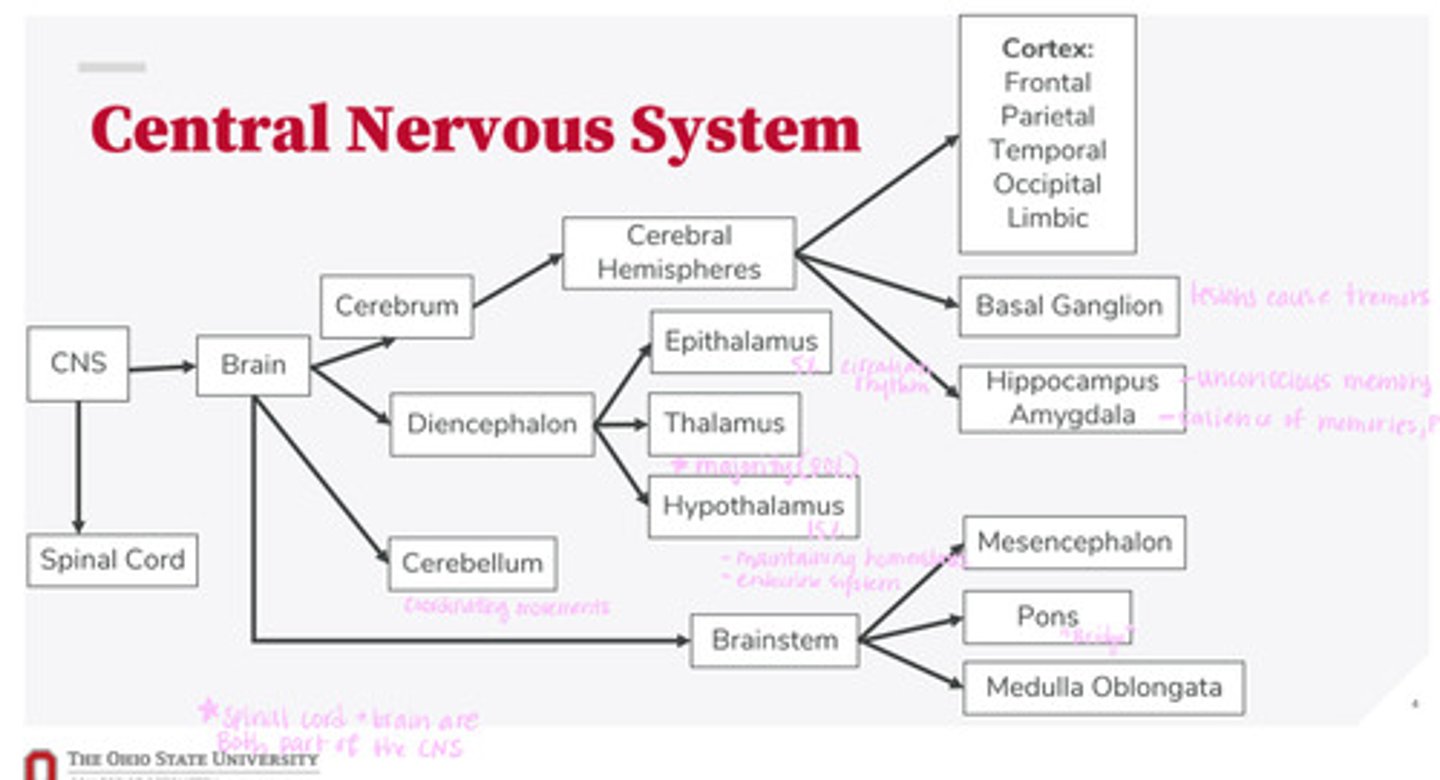

-brain

-spinal cord

What are the 2 divisions of the CNS?

-cerebrum

-diencephalon

-cerebellum

-brainstem

What are the 4 divisions of the brain?

-epithalamus

-thalamus

-hypothalamus

What are the 3 divisions of the diencephalon?

-mesencephalon

-pons

-medulla oblongata

What are the 3 divisions of the brainstem?

-cortex

-basal ganglion

-hippocampus

-amygdala

What are the divisions of the cerebral hemispheres?

-frontal lobe

-parietal lobe

-temporal lobe

-occipital lobe

-limbic system

What are the divisions of the cortex?

coordinating movements

What is the function of the cerebellum?

thalamus

A majority of signals from the diencephalon flow into where?

circadian rhythm

What is the function of the epithalamus?

-maintaining homeostasis

-endocrine system function

What is the function of the hypothalamus?

tremors

Lesions on the basal ganglion cause what?

hippocampus

What part of the brain is in control of unconscious memory?

amygdala

What part of the brain is in control of the salience of memories (PTSD)?

The bridge between the mesencephalon and the medulla oblongata

What is the function of the pons?